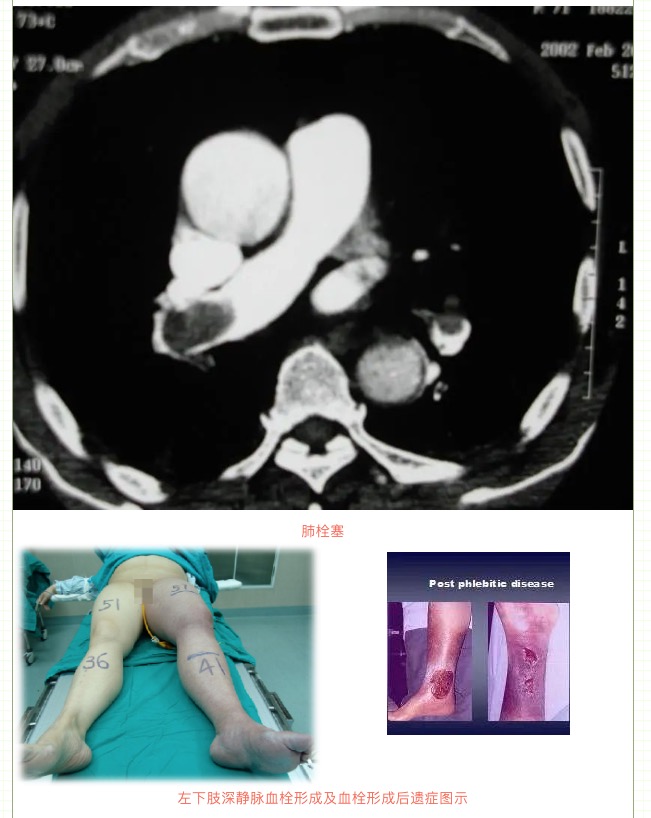

由于下肢靜脈血栓形成導致下肢靜脈血液回流受阻,可能出現(xiàn)單側(cè)腿腫脹、疼痛等表現(xiàn),若出現(xiàn)血栓脫落還可能會導致肺栓塞,嚴重者可危及生命!如果下肢深靜脈血栓形成沒有接受規(guī)范治療,等血栓機化后,有可能會出現(xiàn)下肢反復腫脹(晨輕暮重)、皮膚色素沉著、下肢靜脈曲張等表現(xiàn),這就是深靜脈血栓形成后綜合征,也叫血栓后遺癥。

其中,下肢深靜脈血栓形成就是最典型的靜脈阻塞性疾病。由于血栓形成導致下肢靜脈血液回流受阻,出現(xiàn)一側(cè)腿腫、疼痛等表現(xiàn),同時血栓脫落還會導致肺栓塞,危及生命!

因此,一旦發(fā)現(xiàn)下肢深靜脈血栓形成,建議立即就診,在靜脈濾器保護下進行溶栓治療,預防血栓脫落導致致死性肺栓塞及清除下肢靜脈血栓,防止血栓后遺癥出現(xiàn)。我們的左髂靜脈作為靜脈的重要通道,由于受到動脈和腰椎的壓迫,出現(xiàn)生理性狹窄,因此我們的左下肢相對更容易出現(xiàn)深靜脈血栓、下肢腫脹、下肢靜脈曲張等表現(xiàn),如若出現(xiàn)深靜脈血栓后遺癥或髂靜脈狹窄,必要時需植入髂靜脈支架,避免老爛腿等并發(fā)癥。